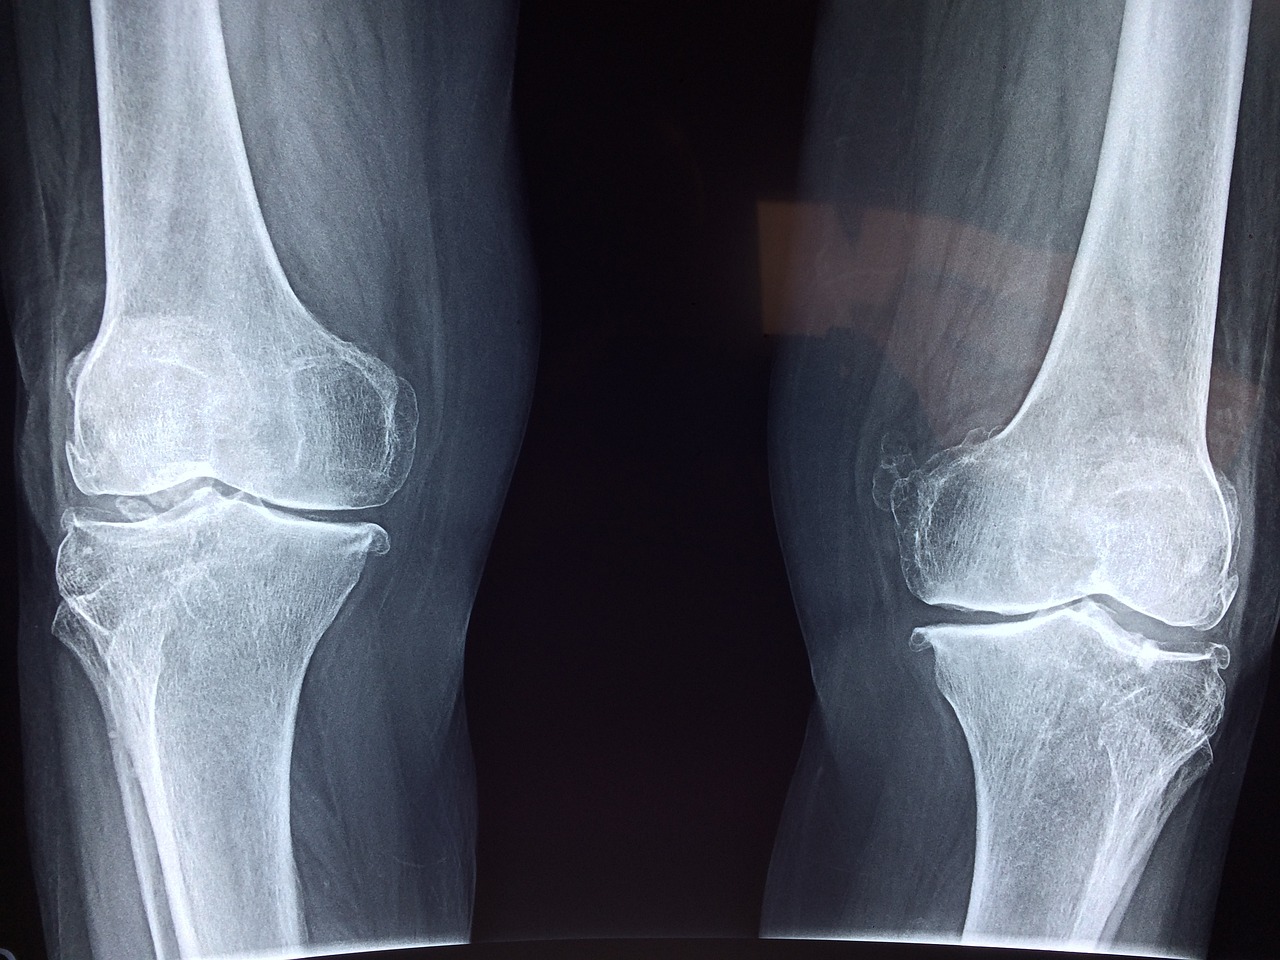

골다공증 어떻게 진단할까?

골다공증은 주로 골밀도 검사를 통해 진단해요. 이 검사는 뼈의 밀도를 측정하여 골다공증의 위험도를 평가하는 방법이에요. 일반적으로 DXA(이중 에너지 X선 흡수법)라는 방법을 사용해요. 이 외에도 의사의 진찰과 병력 청취를 통해 진단할 수 있어요.